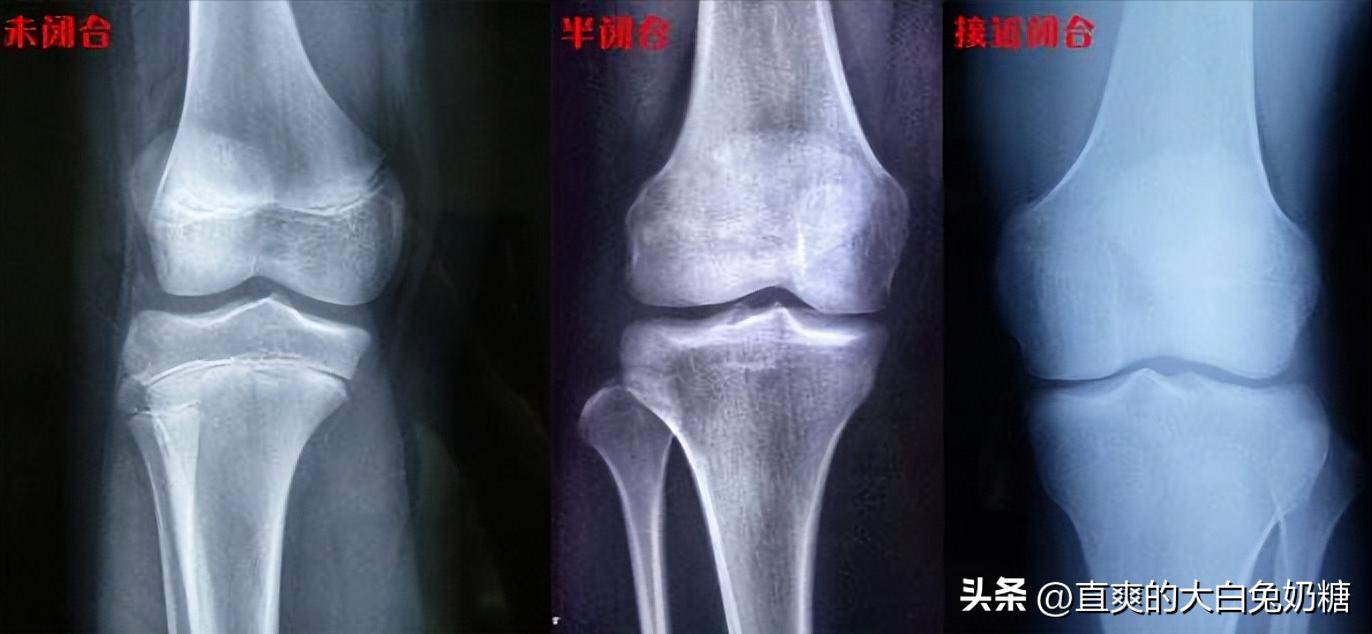

骨骺线图

面对李亚诺的重重威胁,父母只好答应带他到医院拍片检查。果不其然, 李亚诺的骨骺线已经完全闭合,基本没有自然长高的可能性。

李亚诺不肯接受这个现实,便多次换医院检查,但结果却始终一样。